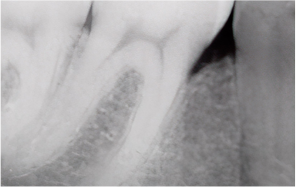

Before & After

Even when severe periodontal disease has caused gingival recession and alveolar bone resorption, teeth can often be preserved through gum regeneration therapy using Emdogain. This procedure regenerates damaged alveolar bone and surrounding periodontal tissue. By applying Emdogain — a specialized gel that stimulates periodontal tissue regeneration — the supporting structures of the tooth are rebuilt, allowing function and health to be restored without extraction.

Across more than 40 clinical studies involving over 1,500 intrabony defects, Emdogain has been proven effective in stimulating new periodontal attachment formation. To date, no adverse effects have been reported in professional clinical use or clinical research.